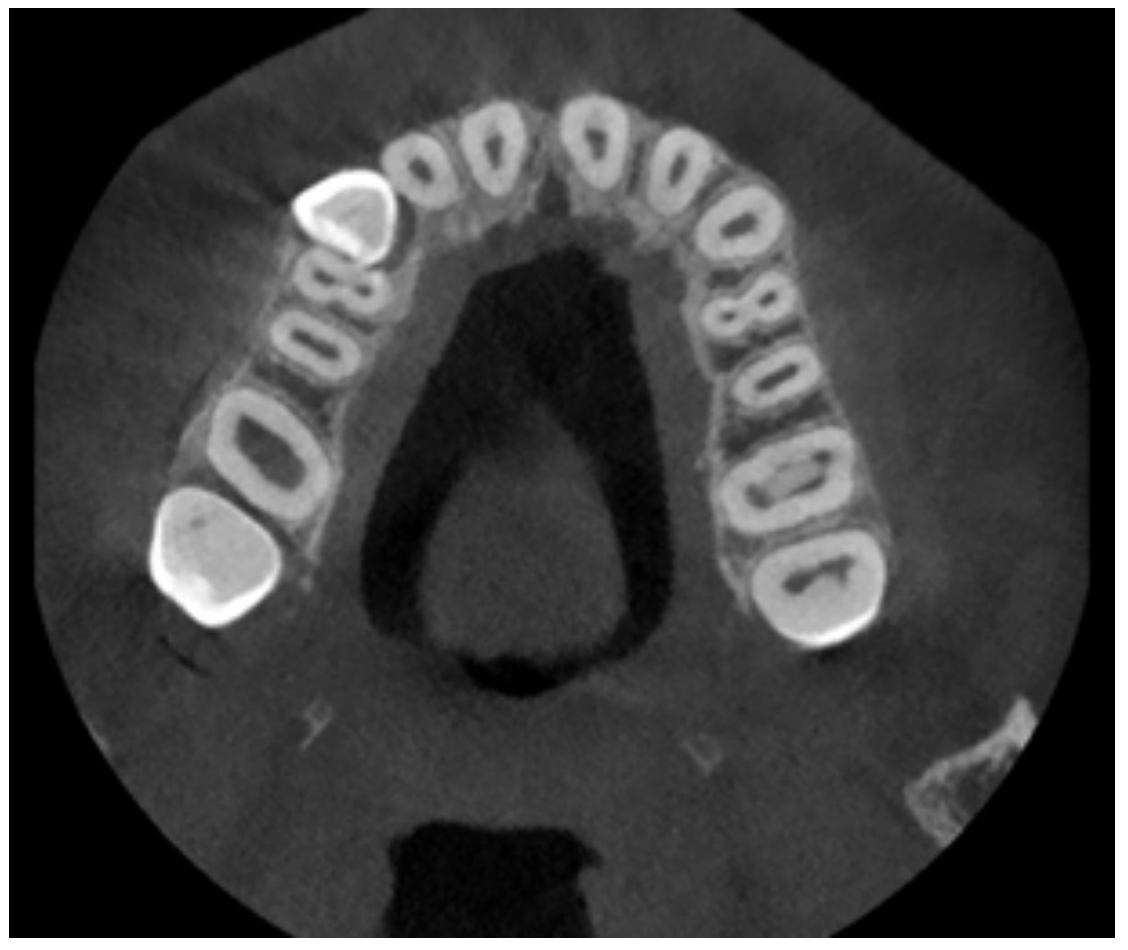

The patient was also analyzed using CBCT investigations. Figure 4 shows representative images of the maxillary.

Figure 4. A tomographic image of the analyzed patient.